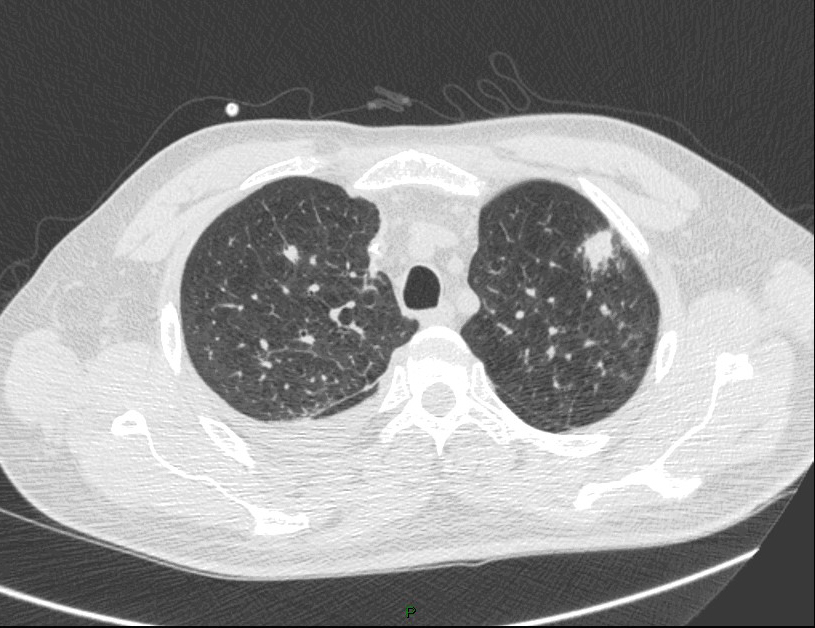

La fièvre persiste malgré les antibiotiques. Cela fait maintenant 5 jours, et vous décidez donc de réaliser un scanner thoracique dont les images sont les suivantes.

Question 13 : Comment décrivez-vous ces images ?

Nodule pulmonaire entouré de verre dépoli

Hypothèse la plus probable devant le terrain de neutropénie prolongée et les images en faveur

Aspergillose pulmonaire invasive = infection fongique invasive la plus fréquente chez le patient avec neutropénie prolongée (> 7 jours de neutropénie).

- imagerie :

°précoce : signe du halo : nodule unique ou multiple, avec verre dépoli autour (signe du grelot se voit dans l’aspergillome compliquant une caverne tuberculeuse par exemple) ;